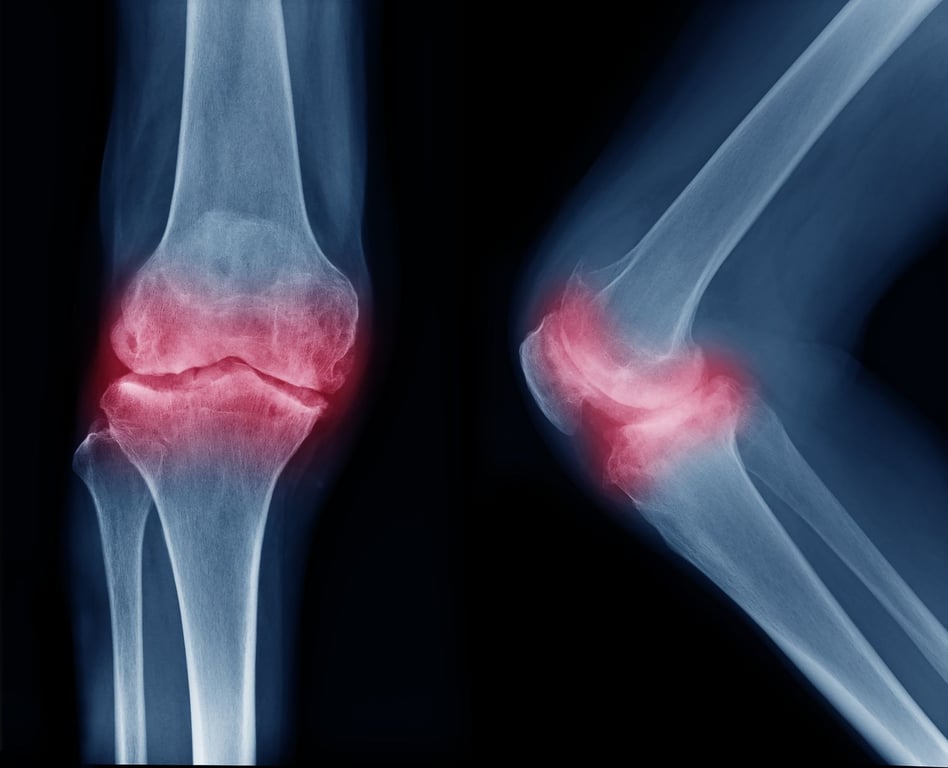

New Biomaterial May Help Regrow Cartilage in Damaged Joints

Scientists at Northwestern University have developed a new bioactive material that could help people regrow cartilage in damaged joints. The substance successfully regenerated high-quality cartilage in the knee joints of a sheep within six months. “Cartilage is a critical component … Continue reading